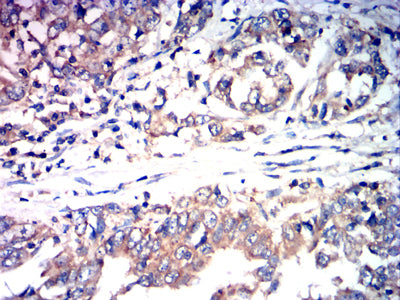

Immunohistochemical analysis of paraffin-embedded human rectal cancer tissues using CCL27 mouse mAb with DAB staining.

Immunohistochemical analysis of paraffin-embedded human stomach cancer tissues using CCL27 mouse mAb with DAB staining.